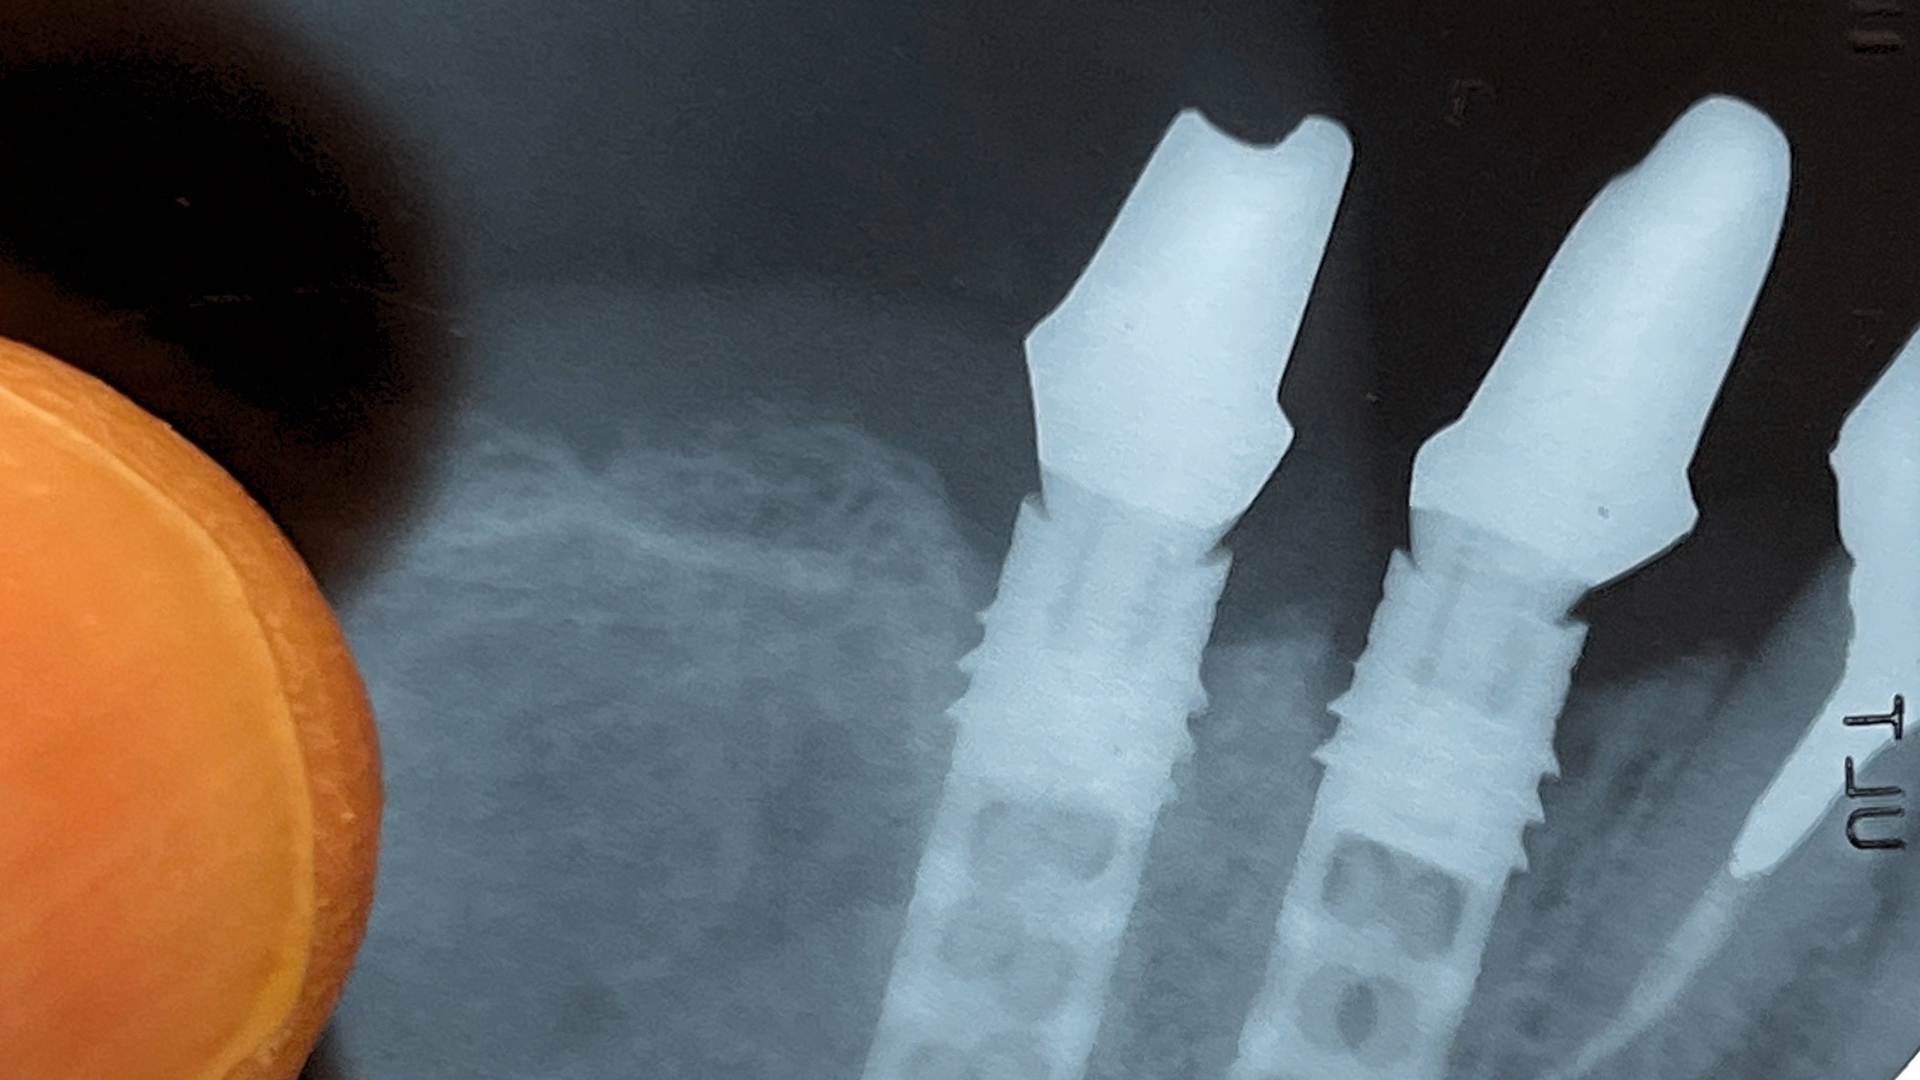

- Radiograph: I always request x-ray images downloaded from the software. (I’d rather not get a picture taken of image on the computer screen.) This allows me to play with the balance, contrast, brightness, and size of the picture, which makes identification so much easier. I have every implant catalog I have ever received from every sales rep in the last four decades for reference.

- Implant interface: Look at the interface rather than the implant body. I can look at any x-ray and expand the interface of the implant and look for internal or external hex. If, for example, it looks like a Brånemark regular-diameter implant, I’m done. If the diameter is wider or smaller, I’ll check the platform versus the hex to further establish which implant company made this diameter of implant. For example, Nobel Biocare had wider- and smaller-diameter implants where the external hex and thread hole are wider to match. 3i had wide and narrow implant platforms with the same external hex and thread hole as the regular diameter. This makes a Nobel Biocare 5 mm implant incompatible with the 3i 5 mm. In the case of the Core-vent Zimmer implant, it’s very easy. The regular has a taper, and the wide implant is flat. The internal hex connection is the same for both sizes. If the implant is an original Core-vent, there will be a hole at the bottom of it. Straumann Tissue Level is the easiest to identify, but some clones have changed the thread and internal connection. In this case, we cannot use Straumann parts but instead need to get the parts designed by the manufacturer of the implant. Unfortunately, many of these companies have long gone out of business.

- Implant body: After identifying the interface, look at the implant itself. Early implants were not threaded. For example, Core-vent’s first implants were cylinders with a hole at the bottom. The Innova Endopore implant was tapered with a porous surface. It’s very recognizable, and a quick comparison to the catalog or internet image can help in identification. This company made a Brånemark- and Straumann-compatible implant. So, even though they no longer exist, you can get the parts.